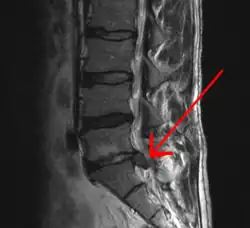

![]() MR-skanning af diskusprolaps. | |

En diskusprolaps er en ryglidelse, hvor en udposning af kernen i en diskus presser mod rygmarvskanalen.